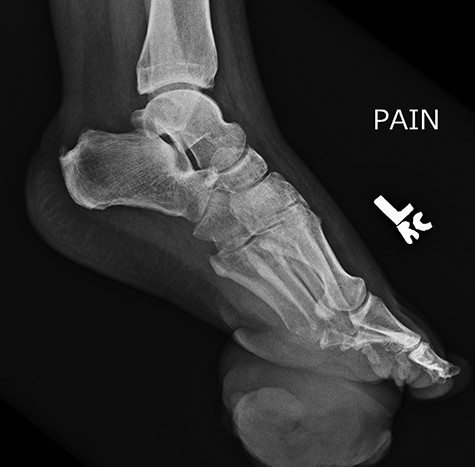

On physical examination, the only significant findings included morbid obesity and a ‘small red tender lesion’ resembling an ‘abscess or fluid collection at the bottom of his foot’ (Fig. 1). X-ray of the patient’s foot was interpreted as ‘soft tissue swelling’ (Fig. 2). The patient was treated with antibiotics for the initial impression of cellulitis and sepsis.

Initial x-ray of the foot was interpreted as ‘soft tissue swelling of the foot’.